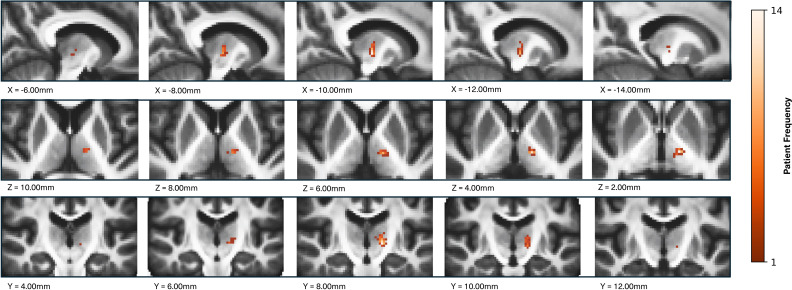

Results: The first 14 consecutive ET patients undergoing MRgFUS at our centre were assessed. Their mean age was 73.6 years and disease duration was 31.8 years. There were significant improvements in treated hand tremor score (60%), disability score (71%) and quality of life (72%) and no clinically relevant side effects at 12 months. A mean of 6.9 sonications was performed and the mean time from first to last sonication was 34.6 min. Greater tremor improvement was observed with lesions in the inferior and lateral part of the Vim.